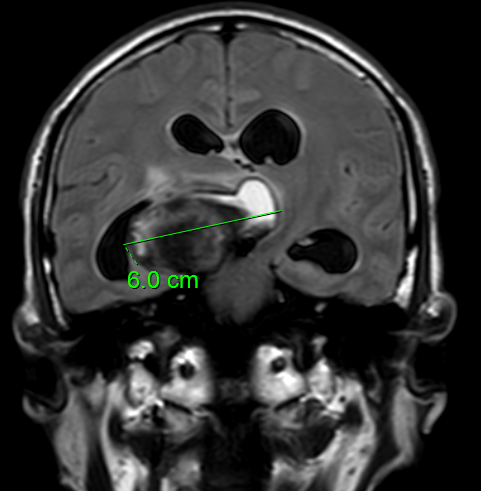

患者年龄62岁,因反复剧烈头痛、精神改变就诊。急诊头部CT提示蛛网膜下腔出血,CTA检查显示其大脑后动脉起始段有一枚6厘米巨大动脉瘤,磁共振进一步提示瘤体囊内血栓形成,已挤压脑组织及神经,引发梗阻性脑积水。“颅内巨大动脉瘤堪称‘定时炸弹’,随时可能引发脑疝,破裂后死亡率极高。”陈亮介绍,患者动脉瘤位置深,且合并高血压病史,手术难度与风险极大。

动脉瘤长径6cm,挤压脑组织致中线移位